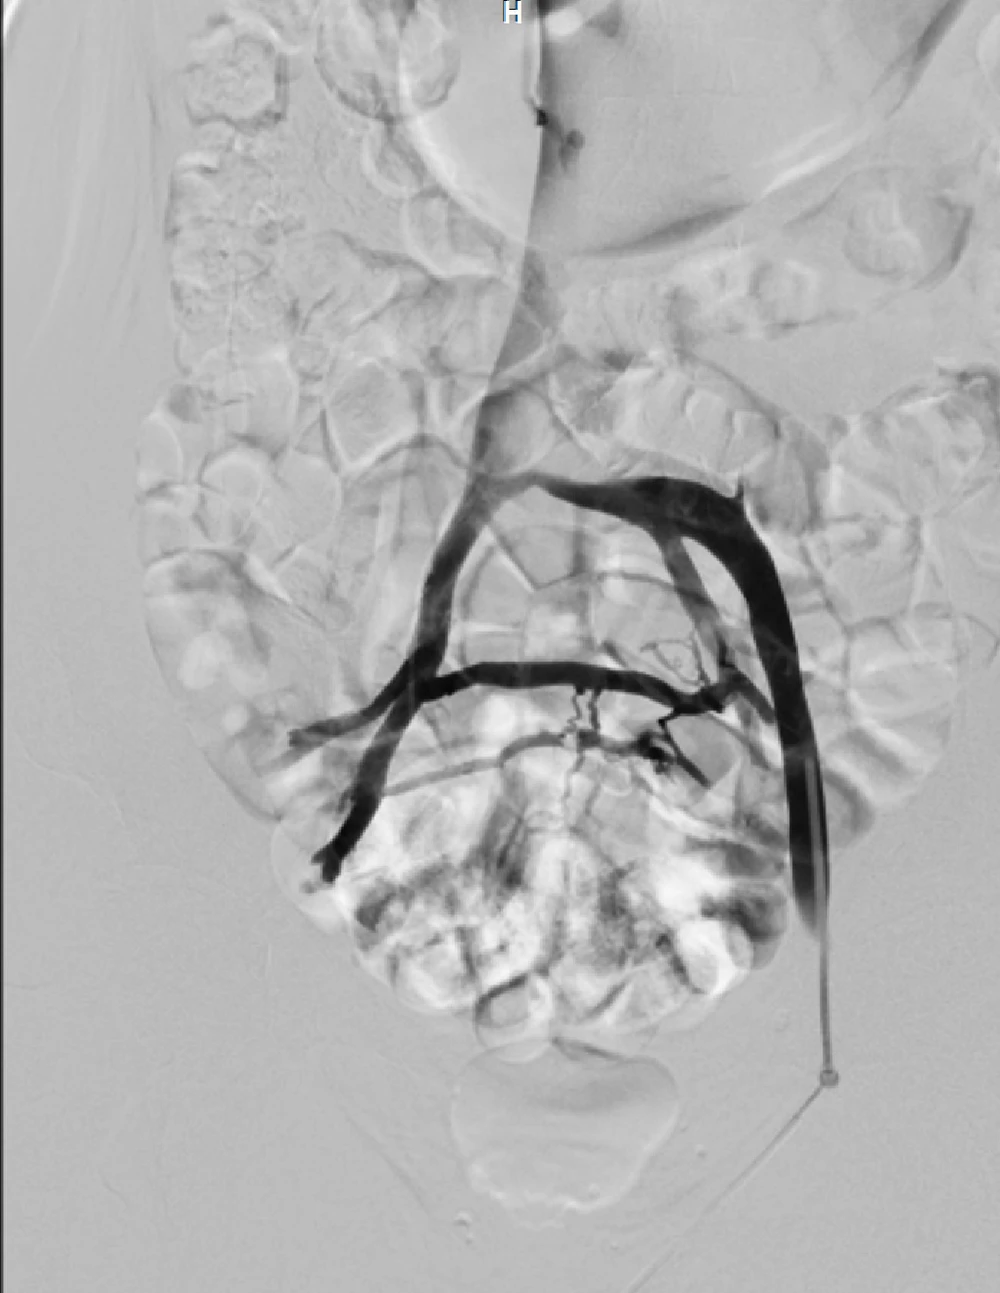

Tại đây, các bác sĩ khoa Lồng ngực mạch máu của BV đã chẩn đoán bệnh có nguồn gốc từ hội chứng chèn ép tĩnh mạch chậu và tắc mạch huyết chân, cần phải điều trị tải thông mạch máu. Sau đó bà G. được nong bóng và đặt stent vào tĩnh mạch chậu, tải thông dòng máu về tim.

Các bác sĩ khoa Lồng ngực mạch máu, BV ĐH Y Dược chẩn đoán bệnh nhân bị suy tĩnh mạch giai đoạn cuối do hội chứng chèn ép tĩnh mạch chậu. Bà H. cũng được điều trị bằng nong bóng và đặt stent tải thông tĩnh mạch chậu thành công.

“Sau mổ, tình trạng phù chân của bà H. giảm rõ rệt. Khoảng 10 ngày sau vết loét lành hoàn toàn và hết đau. Các triệu chứng suy tĩnh mạch khác cũng được cải thiện dần sau đó. Theo dõi đến nay đã hơn hai năm, chúng tôi thấy tình trạng suy tĩnh mạch không tái phát và các kết quả kiểm tra cho thấy tĩnh mạch chậu được tải thông vẫn hoạt động tốt, không tải hẹp” - BS Phong nói.

Theo ThS-BS Lê Thanh Phong, trước đây hội chứng chèn ép tĩnh mạch chặn được điều trị bằng phẫu thuật, rất phức tạp, mất nhiều máu và gây đau đớn. Ngày nay, với sự phát triển của can thiệp nội mạch, hội chứng này có thể điều trị khỏi bằng cách nong bóng và đặt giá đỡ tĩnh mạch (stent) chỉ qua một vết đâm kim vùng bẹn đùi. Người bệnh có thể đi lại vài giờ sau mổ và có thể xuất viện trong ngày.